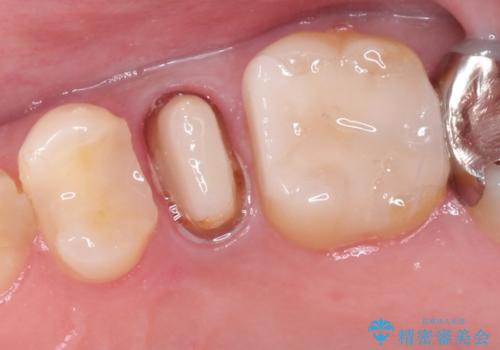

- 左上の後ろから3番目の歯のかぶせ物が適合不良であったので、根管治療を行い、オールセラミックを装着する計画としました。

根管治療からかぶせ物まで精度の高い治療をおこないました。